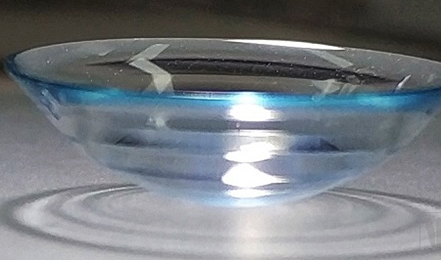

近日,艾康特医疗科技的“VSL硬性巩膜接触镜”顺利通过国家药品监督管理局创新医疗器械特别审查程序,获得产......

动脉网获悉,致力于眼科眼视光领域医疗器械全套创新解决方案的研发生产企业——艾康特医疗科技有限公司(以下简......